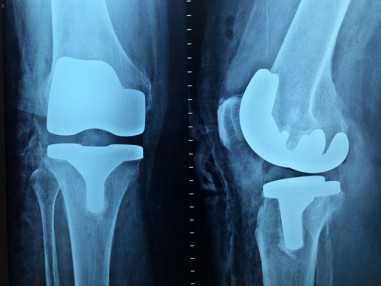

„Az emberi szervezetben kétszáznál több csont van. Ennek megfelelően rengeteg az ízület és az izom, ami bármikor problémát okozhat. És ez csak az a degeneratív része kérdéskörnek, azaz a részben a korral járó mozgásszervi panaszok csoportja. De mindezek mellett beszélni kell még a rengeteg sérülésről, sportsérülésről, valamint a veleszületett betegségekről is” – mondja a főorvos, hozzátéve, hogy az ortopéd orvosoknak a kopások okozta műtétek jelentik a legtöbb munkát. „A mozgásszervi sebészetben az úgynevezett nagyízületi csípő- és térdízületi protézis-beültetések a leggyakoribbak. Mindez annak is köszönhető, hogy az arthosis – azaz az ízületi kopás – okozta életminőség csökkenés, a betegek visszajelzései alapján készített felmérés szerint az ötödik helyen áll. Kétségtelen, hogy amikor minden mozdulat fáj, az eléggé meg tudja keseríteni az ember életét” – hangsúlyozza dr. Böröcz István.

Megtudjuk: az ízületek kopása az emberek korának előrehaladtával szinte elkerülhetetlen. Főleg a bonyolultabb ízületek, mint például a térd és a váll hajlamosak a kopásra, de nagyon sokan szenvednek csípőarthosistól is. „Kevesen tudják, de egy sima sétánál is az ember súlyának közel három-ötszöröse nehezedik mind a csípőre, mind pedig a térdre. Azaz, ha valaki például 10 kilogramm pluszsúllyal él, akkor minden lépésénél 30–50 kilogrammnyi plusz terhet rak a csípőjére és a térdére. És akkor még nem is beszéltünk a sétánál komolyabb mozgásmódokról” – mondja a főorvos, kiemelve: mivel az elhízás nemcsak Magyarországon, hanem világszerte nagyon komoly gond, ez nagy kihívást jelent az ortopéd szakorvosok számára is.

A protézisek pontos összetételét egyébként nem lehet tudni, mivel azt a gyártó cégek titkosan kezelik. A leggyakoribb azonban a rozsdamentes acél, a titán, valamint a króm-vanádium-molibdén ötvözet. A protézisek műanyag részei pedig magas kopásállóságú polietilénből, illetve a csípőprotézis fejek kerámiából készülnek. Ez utóbbi alatt nem porcelánt kell érteni, hanem egy olyan alumínium ötvözetet, amely csökkenti a protézis kopását, s ennek is köszönhető, hogy a testbe beépített szerkezetek élettartama jelentősen megnövekedett, akár másfél-két évtizeden keresztül is képesek tökéletesen működni.